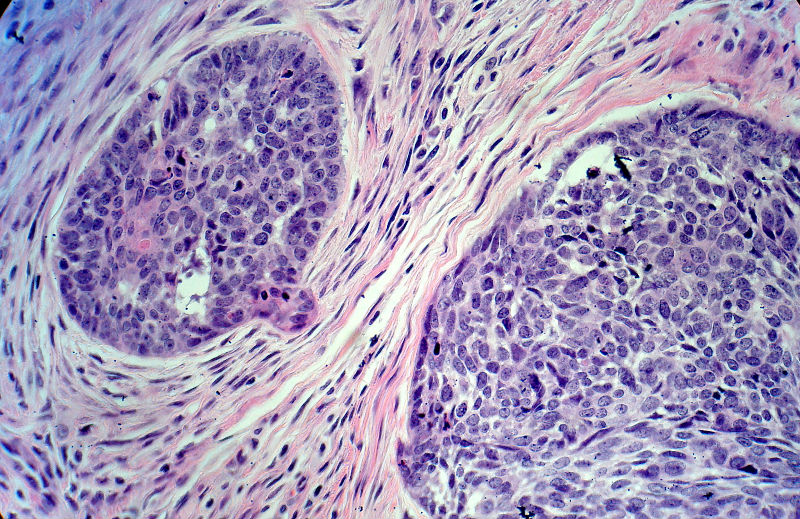

男,49岁,后枕部肿物3年,偶有破溃出血。

大体:皮肤半球形隆起,大小约2.3×2厘米,高出皮表0.8厘米,切面灰白,质地细腻。